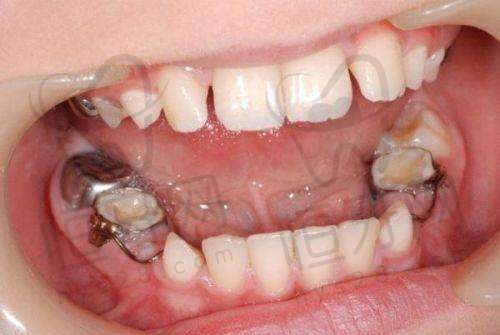

2. **儿童齿科特色**:门诊部打造卡通主题儿童诊室,充满了童趣和温馨。在这里,开展了乳牙预成冠、窝沟封闭等预防性项目。乳牙预成冠可以保护乳牙,防止龋齿进一步发展;窝沟封闭则可以有效预防儿童恒牙龋齿的发生。门诊部还配备了儿童行为诱导专精团队,他们通过游戏化的看牙流程,如播放动画片、讲故事等方式,缓解孩子的就诊焦虑,让孩子在轻松愉快的氛围中完成口腔治疗。该门诊部还被评为金华市儿童口腔健康定点单位,这是对其儿童齿科服务的高度认可。